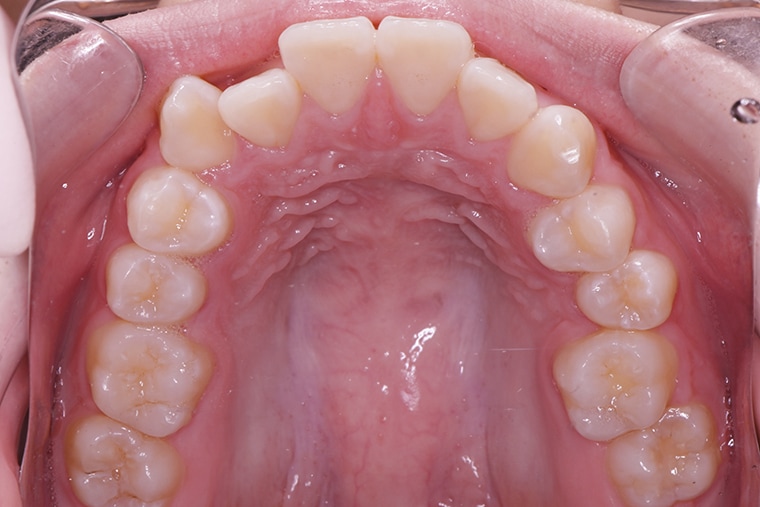

BEFORE